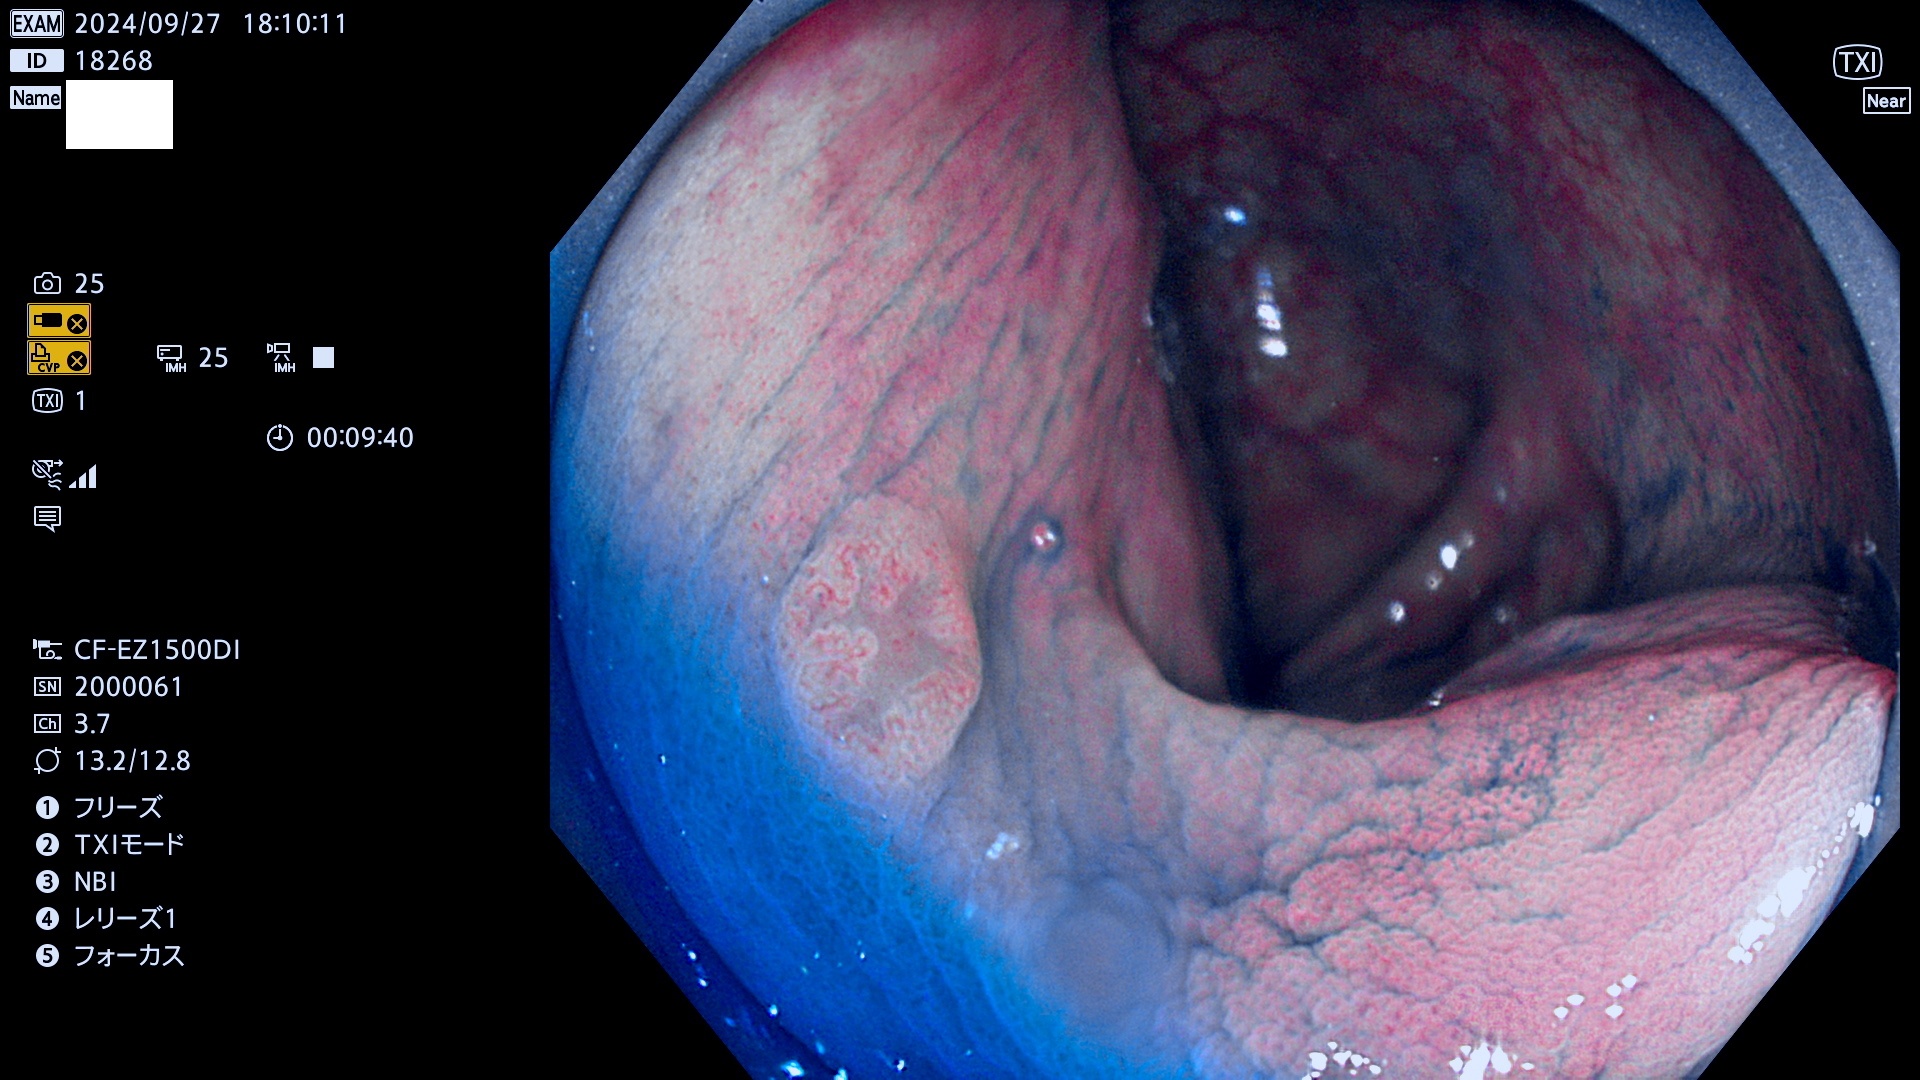

今週のUb、Uc型腺腫

完全に平坦な物をUb、陥凹している物をUcと呼びます。最も発見が難しく危険な病変です。

毎週の検査(木・金・土・日)に発見されたUb、Uc型・腺腫を、その週の日曜の夜にUPし1週間、提示します。

抽出の対象期間 2024年9月26日〜9月29日の4日間(48件の検査)12件 (12/48=25%)